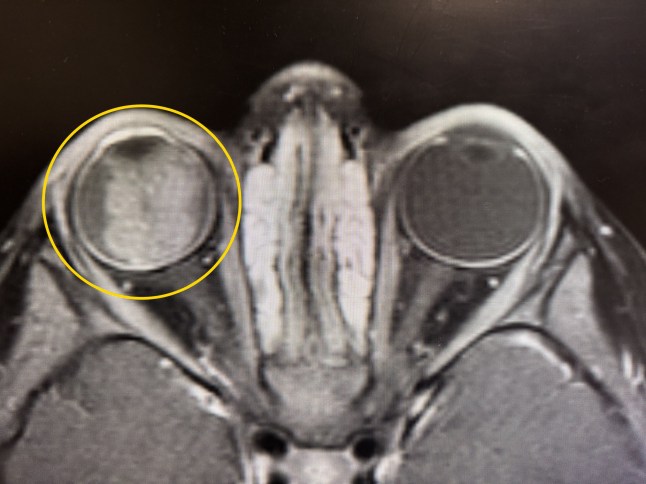

An ultrasound and MRI revealed the tumour behind the eye which covered her Miley’s entire eyeball, and doctors told the parents it was ‘blastoma stage E, which is the worst’.

PIC FROM Kennedy News and Media (PICTURED: MILEY DRAIME, 2, HAD TUMOUR LURKING BEHIND EYE) A mum claims a baby monitor saved her tot's life after it revealed a 'glow' in her pupil - that turned out to be cancer. Kristen Draime was concerned about her daughter Miley Draime when she noticed her left eye 'wandering' in September 2025 and booked an appointment with a doctor. Initially reassured it wasn't anything to worry about, the paediatrician referred Miley for a December appointment with an ophthalmologist to rule out anything more serious. DISCLAIMER: While Kennedy News and Media uses its best endeavours to establish the copyright and authenticity of all pictures supplied, it accepts no liability for any damage, loss or legal action caused by the use of images supplied and the publication of images is solely at your discretion. SEE KENNEDY NEWS COPY - 0161 697 4266

The MRI shows the left eye with a white mass in it which is the retinoblastoma (Picture: Kennedy News and Media)